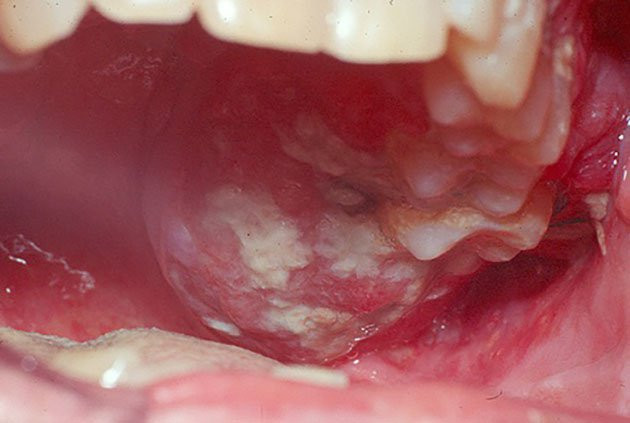

1. Người bị loét miệng lâu năm Đối với nhiều người, lở loét miệng là chuyện thường xuyên xảy ra. Nhiều khi chúng ta chỉ đơn giản là uống một số loại thuốc chống viêm, triệu chứng sẽ đỡ hẳn.

Đối với nhiều người, lở loét miệng là chuyện thường xuyên xảy ra. Nhiều khi chúng ta chỉ đơn giản là uống một số loại thuốc chống viêm, triệu chứng sẽ đỡ hẳn.

Thế nhưng, nếu triệu chứng lở loét miệng diễn ra thường xuyên thì chứng tỏ nó đã kháng lại nhiều loại thuốc và vi khuẩn có lợi, nếu không chú ý thì chúng ta có thể mắc bệnh ung thư miệng, cực kỳ nguy hiểm.

4. Người thích hút thuốc và uống rượu Chỉ cần bạn hút thuốc và uống rượu thì về cơ bản loại bệnh nào cũng có thể xuất hiện. Thực tế, những thói quen này rất có hại cho cơ thể chúng ta, đặc biệt là nếu hút thuốc trường kỳ và nghiện rượu thì tỷ lệ ung thư miệng rất cao.

Chúng ta đều biết câu nói "bệnh từ miệng mà ra", vì vậy vẫn mong rằng mỗi người phải thay đổi những thói quen xấu trong chế độ ăn uống và bổ sung đầy đủ dinh dưỡng cho mình, tất nhiên là phải bổ sung kịp thời.